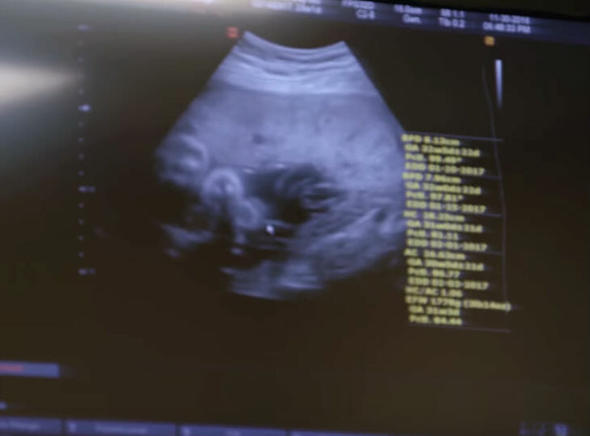

Bryan ve Hayleigh’nin planlarında çocuk sahibi olmak yoktu. Boyundan dolayı doktorlar, hamile kalmasının onun için riski olduğunu söylemişlerdi.

Son derece riskli olan durum doğumdan önce ve sonra kanamalara neden olabilirdi. Hayleigh paniğe kapıldı.

Neyse ki doğum başarılı geçti. Sevgililer gününde Bryan ve Hayleigh’nin kızları Kaia dünyaya geldi. “Dünyanın en tatlı bebeği. Hep uyuyor ve sarılmaya bayılıyor” dedi.